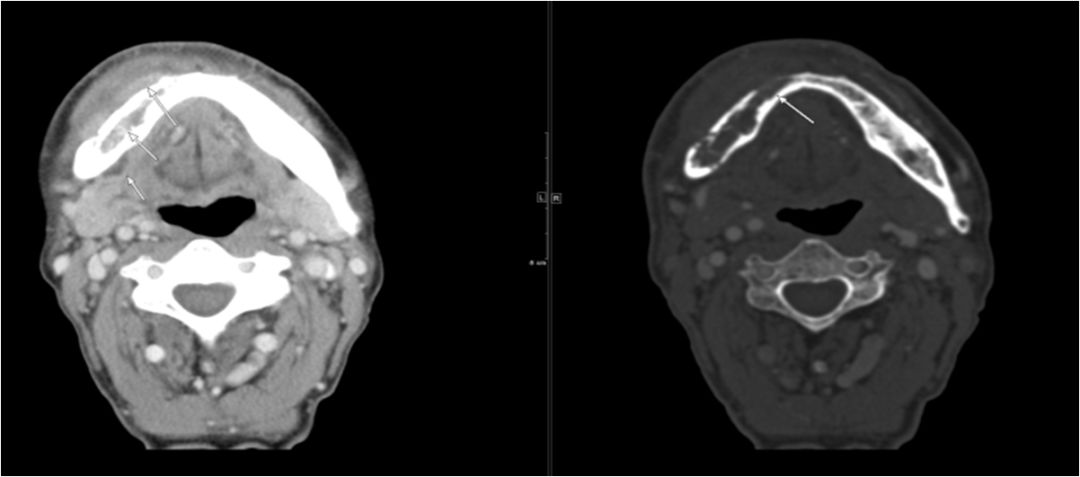

03 眶下间隙、颊间隙、咀嚼肌间隙、翼颌间隙

男,41岁,4天前右上后牙疼痛,右侧面部肿胀3天余。